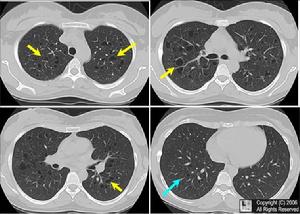

郎格細胞組織細胞增生症2、X線檢查:對診斷很有幫助,不少病例系由X線檢查最先發現。(1)胸部:肺部是最易受累的器官之一。典型改變為肺野透亮度減低呈毛玻璃狀,兩肺彌散的網狀或網點狀陰影,或在網點狀基礎上有局限或彌散的顆粒陰影,須與粟粒性結核鑑別。嚴重者可見彌散性小囊腫、肺氣腫、氣胸、縱隔氣腫或皮下氣腫等,嬰幼兒常見胸腺腫大。(2)骨骼:病變部位呈蟲蝕樣改變至巨大缺損,為溶骨性鑿穿樣損害,形狀不規則,呈圓或橢圓形。脊椎多表現為錐體破壞偶見椎旁膿腫。下頜骨浸潤時牙槽硬板及支持骨破壞,出現漂浮齒徵象。